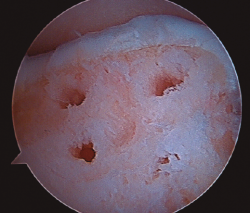

- Inicialmente procedemos a retirar el cartílago inestable, el hueso necrótico y la capa superior calcificada mediante un sinoviotomo, fresa motorizada, junto con instrumental de curetaje artroscópico (Figura 1).

- Posteriormente, realizamos la técnica de estimulación seleccionada entre: brocado o microperforaciones o nanoperforaciones. Preferimos realizar estas últimas a perforaciones más grandes que pueden dañar el hueso subcondral u otras técnicas de brocado con agujas de Kirschner que pueden producir necrosis inducida por el efecto térmico (Figura 2). Cada “nanofractura” debe realizarse separada 3-4 mm con una profundidad de 9-10 mm y un diámetro de 1 mm.

Figura 2. Técnica de estimulación medular con nanofracturas. Obsérvense los bordes del curetaje y la cruentación de la capa mineralizada.